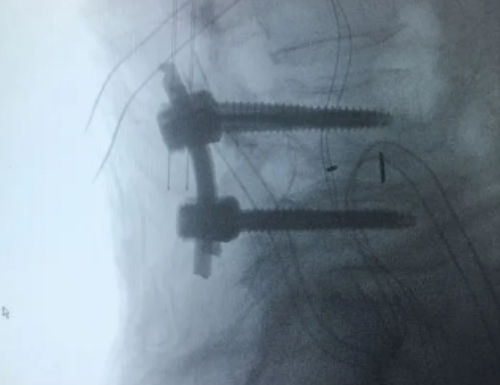

我做的是腰椎间盘融合手术,就是把两个骨节固定在一起。这样以后弯腰会有一定的影响,但是及时效果很强,麻药退去之后我能明显地感受到下半身恢复了力量,屁股也不疼了。

可是医生告诉我,由于我的体重太大,使用了 4 钉 2 棒,会在一定程度上影响生活。

并且由于钢板无法被人体吸收,如果长年在人体内,很有可能被血液或其他什么东西侵蚀,所以一年半之后,我必须再做手术取出固定用的钢板。

传统手术:如腰椎融合术等。